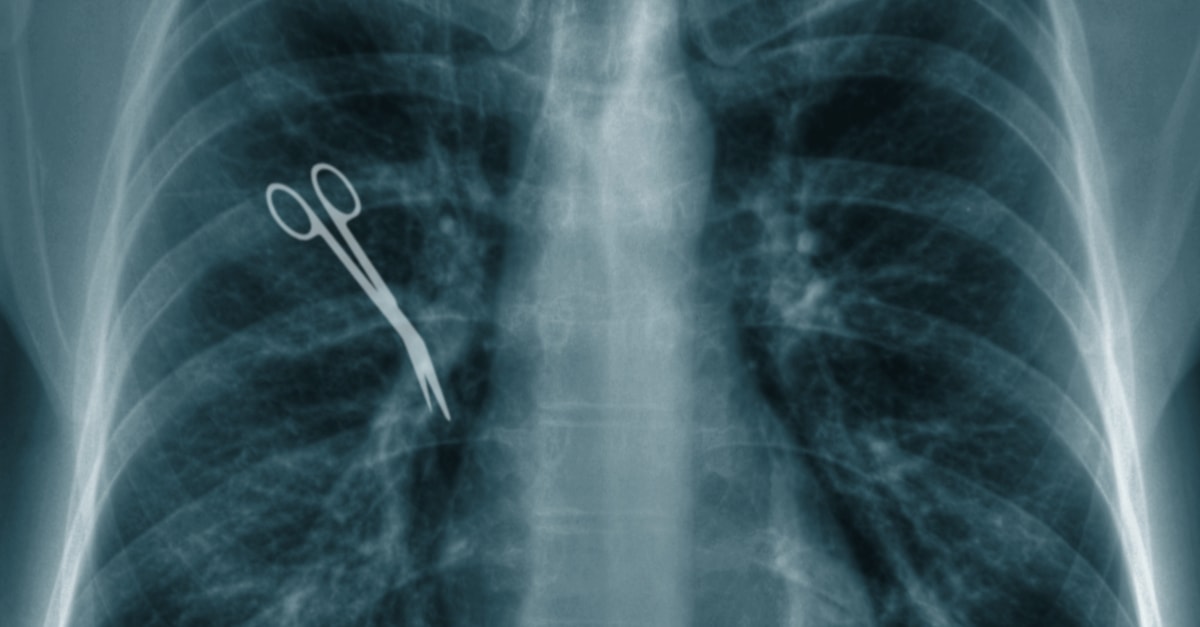

W zależność od przeprowadzanego zabiegu w ciele ludzkim może pozostać jeden z aż 250 narzędzi wykorzystywanych do standardowych operacji. Większość takich przedmiotów jest niewielka, używana w sposób mechaniczny i szybki, zdarza się zatem, że pozostają w ciałach powodując późniejsze kłopoty zdrowotne. Wśród nich znajdziecie między innymi:

- nożyczki

Najczęsciej w ciałach pacjentów zostają gąbki oraz igły. Te pierwsze są wbrew pozorom łatwe do “zgubienia” ponieważ szybko nasiąkając krwią i innymi płynami ustrojowymi wtapiają się w “krajobraz” tkanek i organów pacjenta. Najczęstszymi miejscami, gdzie pozostają przedmioty są podbrzusze oraz klatka piersiowa, choć notowane są przypadki także na przykład pozostawienia “pamiątek” w waginie. Przyczyną jest najczęściej przemęczenie i związana z tym nieuwaga lekarzy i asystentów. Ryzyko jest znacznie większe, gdy na jednym pacjencie przeprowadza się szereg zabiegów, ma on zbyt wysoką masę albo zabiegi wiążą się ze sporą utratą krwi.